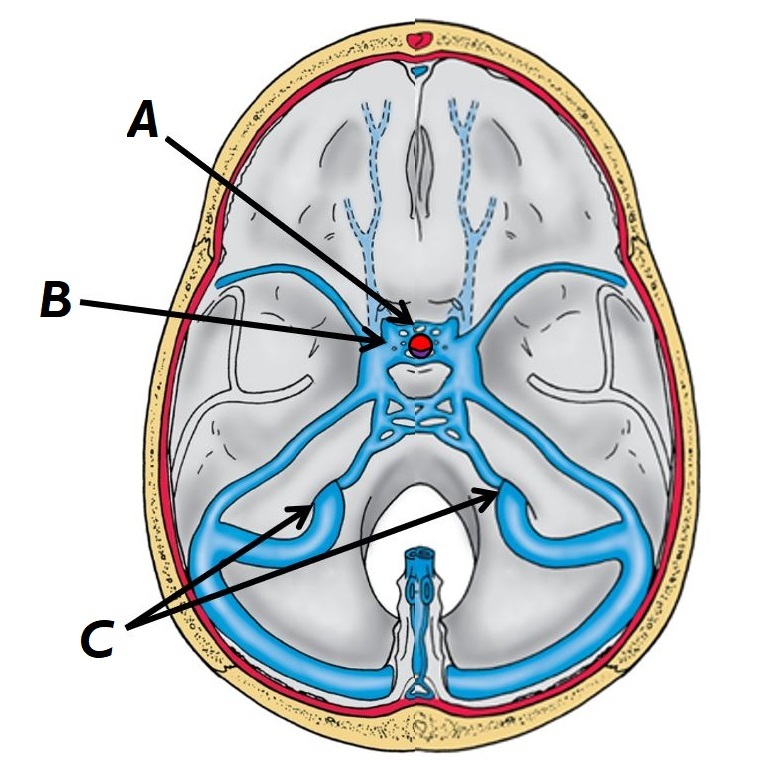

Name structures A, B and C

A - Left internal carotid artery

B - Basilar artery

C - Left vertebral artery

Name structures A, B and C

A - Anterior intercavernous fossa

B - Left cavernous sinus

C - Dural venous sinuses